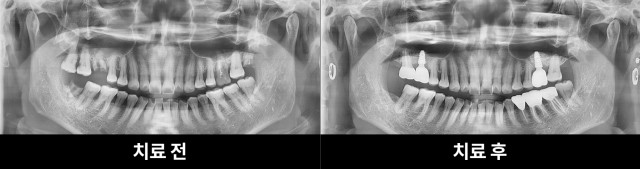

[200602 ~ 210209] 김**님 치료과정

2022-12-09